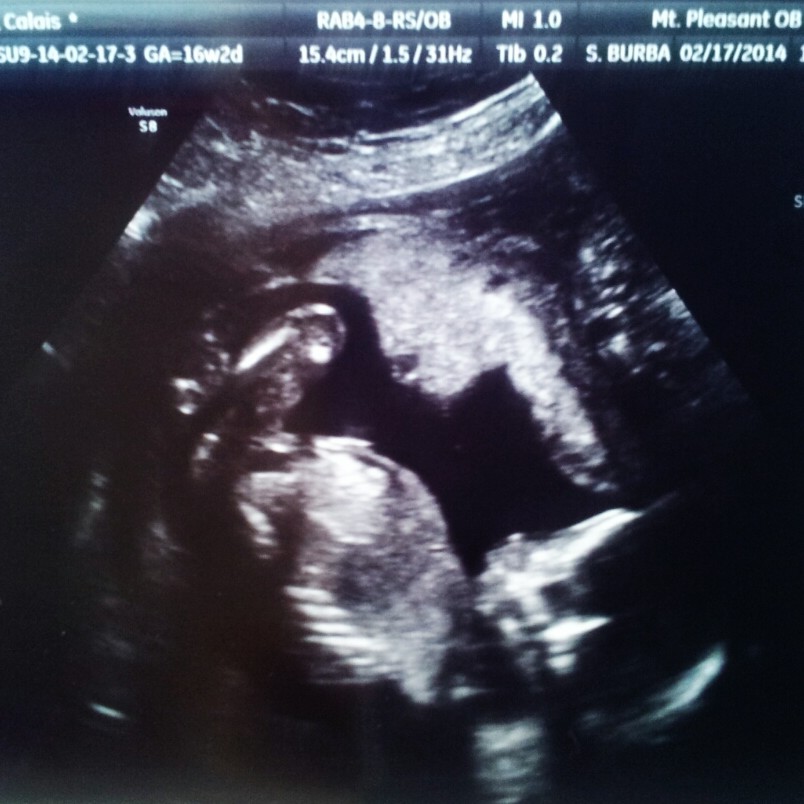

Just wondering....what's making everyone say boy? Im kinda confused by the second white line on top of the nub in the nub picture but i feel like the potty shot looks very boy because tge only line on the nub seems to be a faint horizontal one.

because you are at a pretty darn early stage of gestation for nub guessing, but the little nub is already starting to go up, and that is only going to continue to go up as you get further along over the next two weeks. If nub is already up at 12 w 2 d that is a good sign for a boy. Looks very boy to me.

The potty shot doesn't mean anything at 12 weeks, but the nub shot is very boyish to me...has the "bump" on the end of the nub which is a strong boy indication! And atomic is right, the angle is up and while boy nubs can be flat at this early stage before they start to move up (my DS3's was), in my experience girl nubs are almost never angled up. In other words, us boy moms have to hold our breath when we get girly nubs (although some girl nubs are very obvious if they point down a lot) to hope they don't change, while a boyish looking nub rarely changes to flat...kwim? HTH :)

Your baby's nub has the famous "boy bump" on the end! ;)

I've been stressing over what looks to be a straight flat nub in one of these pics (top picture) all day. I do still see the original "angled nub" in the background but im not sure what that flat line would be? The bottom pic is even more confusing to look at. Lol Im driving myself crazy....anyone see what im seeing?

Those are bones in the legs, not a nub.

The original pictures you posted are pretty much unquestionable 'boy' parts.